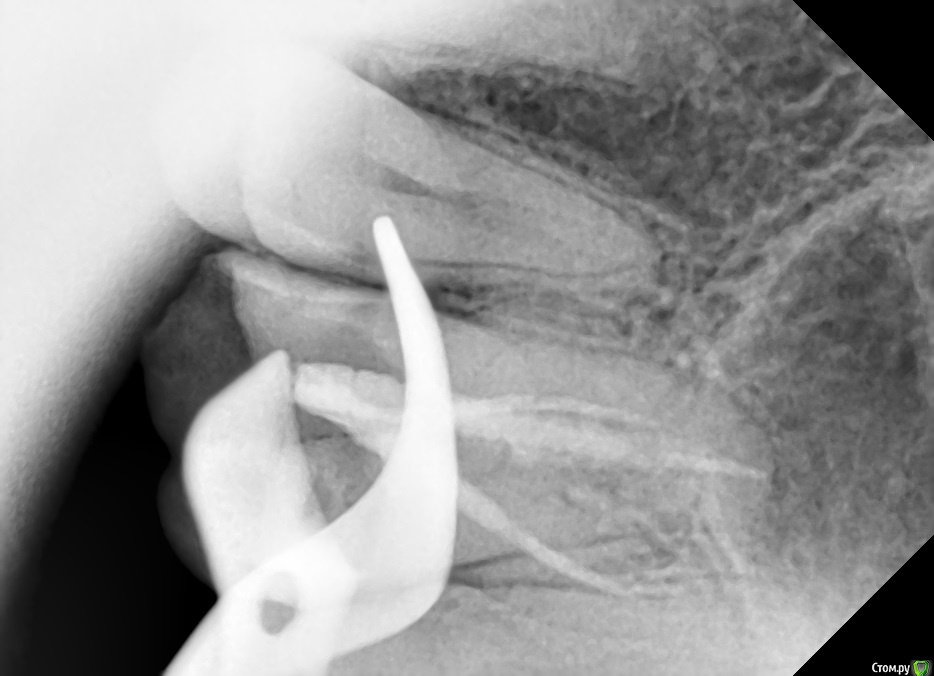

boeing Опубликовано 6 марта, 2019 Автор Поделиться Опубликовано 6 марта, 2019 (изменено) Супруга была на приеме у неск. врачей, сделан прицельный снимок. По КТ и по снимку воспаления нет, почему болит сказать не могут. Болит по разному - то 6-ка, то имплант, то все вместе. Также переодически немного побаливают и другие (здоровые зубы). Один врач предположил что это неврологическая проблема. Подскажите, как лучше поступить, что делать с 6-кой? Один врач говорит что варианта 2 - [перелечивание под микроскопом с извлечением штифтов + коронка] либо [удаление+имплант], по стоимости примерно одинаково. Изменено 6 марта, 2019 пользователем boeing Ссылка на комментарий